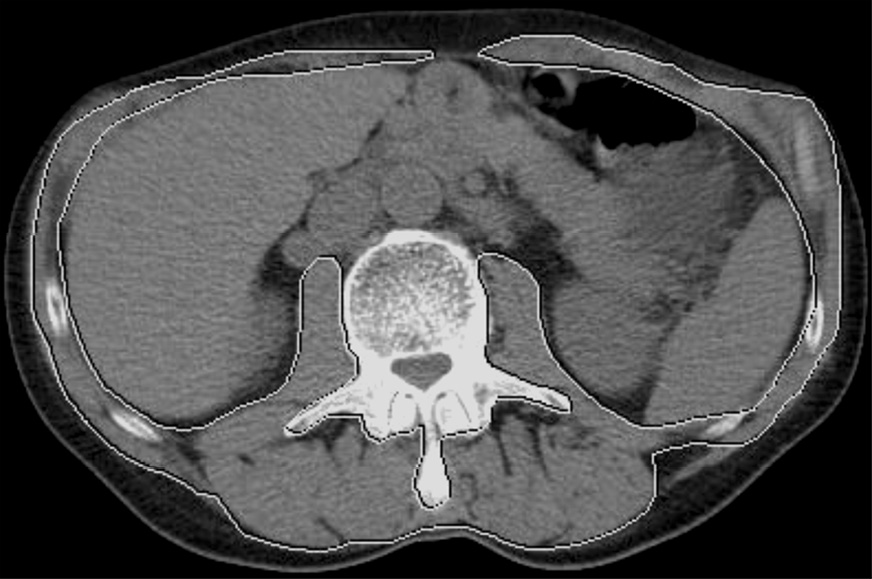

Степень послеоперационных осложнений оценивали согласно классификации Clavien–Dindo [13] (рис. 1).

Рис. 1. Пациент Л. Случай единственного летального исхода. КТ-саркометрия на уровне LIII позвонка до операции. Площадь выделенной зоны – 129,77 см2, СМИ – 31,5 см2/м2. Саркопения.

Fig. 1. Patient L. The only fatal case. Computed tomography sarcometry at the LIII level of the vertebra before surgery. The area of the marked zone is 129.77 cm2, and the skeletal-muscular index is 31.5 cm2/m2. Sarcopenia.